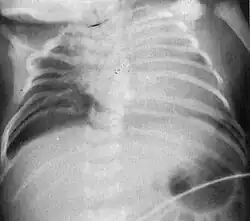

Radiograph depicting typical skeletal features of Jarcho-Levin syndrome, subtype spondylothoracic dysplasia. Note fanlike configuration of the ribs, with extensive posterior fusion, along with multiple vertebral segmentation defects.

Spondylothoracic dysplasia, or STD, has been repeatedly described as an autosomal recessively inherited condition that results in a characteristic fan-like configuration of the ribs with minimal intrinsic rib anomalies. Infants born with this condition typically died early in life due to recurrent respiratory infections and pneumonia due to their restricted thorax.[3][4][5] Recently, a report[6] has documented that actual mortality associated with STD is only about 50%, with many survivors leading healthy, independent lives.